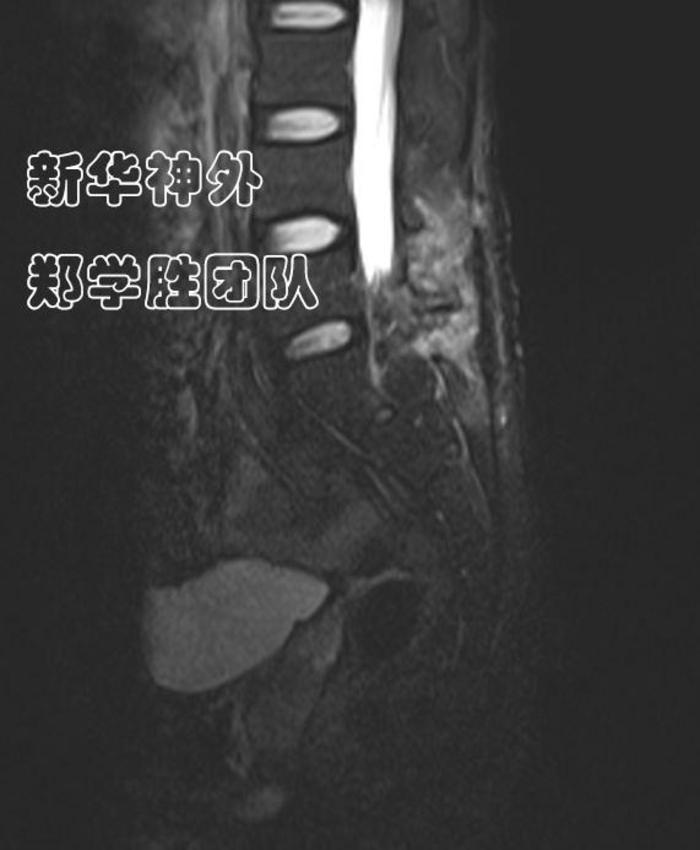

术前MRI显示:8cm巨大腰骶管囊肿;

水往低处流,难道漏口在腰5上段吗?

经过仔细读片,郑学胜主任判断,骶管囊肿漏口很可能在腰5骶1间隙(箭头所指),而不是在腰5上段。